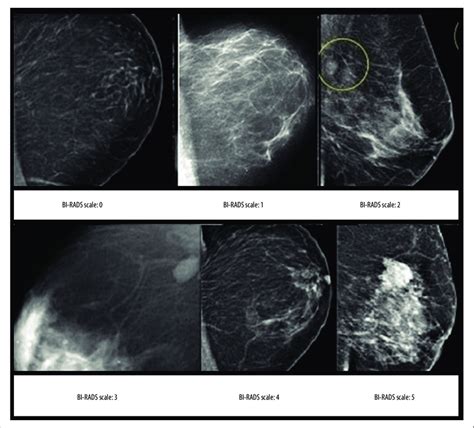

Birads Illustre Breast Imaging Reporting And Data System

Title: - Birads Illustre Breast Imaging Reporting And Data System